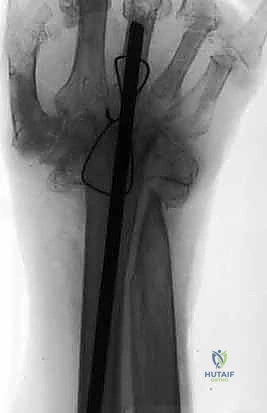

3. تحضير الطعم العظمي (Bone Grafting)

لتحفيز وتسريع عملية التحام العظام (Fusion)، يتم وضع طعم عظمي في الفراغات بين العظام. يمكن أخذ هذا الطعم من نفس منطقة العملية (العظام المزالة محلياً مثل عظم الكعبرة)، أو في بعض الحالات، يتم أخذ قطعة صغيرة من عظم الحوض (Iliac Crest Bone Graft) لغناها بالخلايا الجذعية، أو استخدام بدائل العظام الصناعية.

4. وضع الرسغ في الزاوية الوظيفية المثالية

لا يتم تثبيت الرسغ بشكل مستقيم تماماً. بدلاً من ذلك، يقوم الدكتور هطيف بتثبيته في وضعية "البسط الخفيف" (Slight Extension)، عادة بزاوية تتراوح بين 10 إلى 15 درجة للخلف. هذه الزاوية هي الوضع الطبيعي لليد عند الإمساك بالأشياء بقوة، وتضمن للمريض أقصى قدرة على استخدام يده في حياته اليومية (مثل الإمساك بكوب، أو استخدام الأدوات).

5. التثبيت بالشريحة والمسامير (Plate Fixation)

يتم استخدام شريحة معدنية خاصة (Wrist Fusion Plate)، غالباً مصنوعة من التيتانيوم، مصممة خصيصاً لتناسب تشريح الرسغ. يتم تثبيت هذه الشريحة بمسامير قوية تمتد من عظم الكعبرة في الساعد، مروراً بعظام الرسغ، وصولاً إلى العظم المشطي الثالث (Third Metacarpal) في اليد. هذا التثبيت الصلب يمنع أي حركة ويسمح للعظام بالالتحام لتكوين كتلة واحدة صلبة.